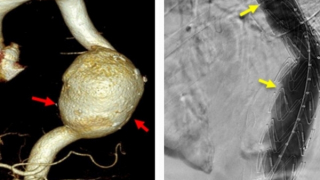

Cứu sống bệnh nhân người Campuchia bị vỡ túi phình khổng lồ động mạch chủ bụng